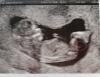

Присмотрелась я тут в фото с 1 скрининга, и мне кажется я знаю пол)

(на узи не предполагали, сказали рано ещё)

Как думаете, мальчик или девочка? 😁

Мне кажется мальчик...я кажется у своего на первом скрининге такую же пипирку смотрела)))потом на остальных подтверждалось. На 2ом там всё показали)